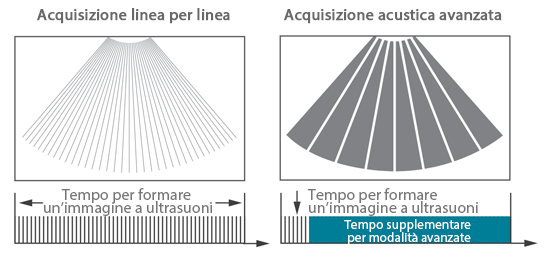

Fin dalla sua fondazione Mindray esplora continuamente nuovi modi per migliorare l'affidabilit├Ā diagnostica. Equipaggiata con la pi├╣ rivoluzionaria tecnologia ZONE Sonography?, la nuova piattaforma ZST+ di Resona 7 porta la qualit├Ā dell'immagine ecografica ad un livello superiore con l'acquisizione per zone e l'elaborazione dei dati canale.